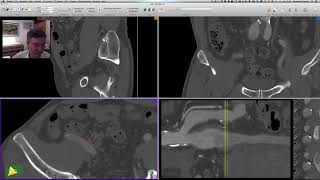

Como medir comprimento de superfícies 3D no OsiriX usando a ferramenta Surface Length.

Inscreva-se no Canal Ver Todas as AulasComo medir comprimento de superfícies 3D no OsiriX usando a ferramenta Surface Length.